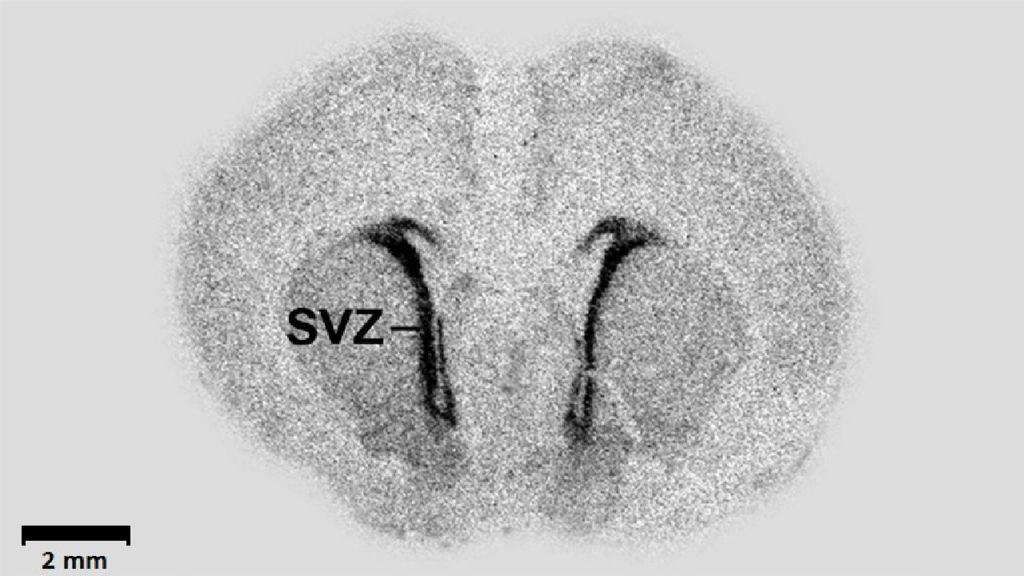

Слайд 8

Изображение слайда

Слайд 9

Слайд 10

В зубчатой извилине гиппокампа выделяется субгранулярный слой, в котором находятся клетки-предшественники нейронов, то есть нервная стволовая ткань. Нервная стволовая ткань